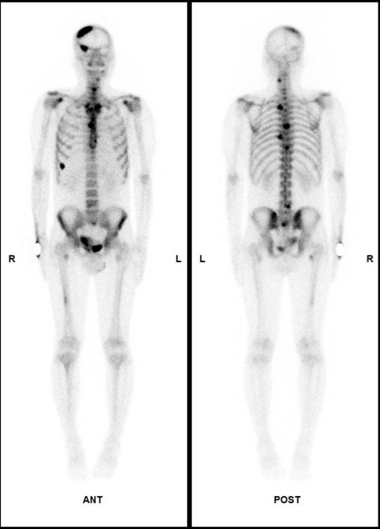

骨骼系统:

骨骼健康吗?

SPECT/CT骨显像不仅常用于评估肿瘤患者有无骨转移以进行肿瘤分期评估,且在隐匿性骨折、股骨头缺血性坏死、人工关节术后随访评估以及关节炎性病变等骨关节疾病中也有其独特价值。骨显像能早期发现病变,敏感性高,一次检查即可进行全身骨骼情况评估。

案例:胰腺癌患者为评估有无骨转移行全身骨显像,检查结果提示全身骨骼多发转移。